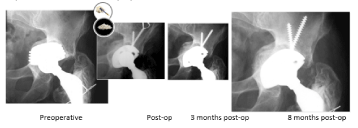

Case 4 - Paprosky Type 2c

Case description / anamnesis: 80-year-old male

Right acetabular cup mobilization 18 years postoperative (figure 7).

Figure 7. Case 4 - Paprosky Type 2c

Defects were characterized by a feicient medial wall (tear drop) causing direct medial migration of hip center. The superior dome is intact, presenting vertical deplacement.

Treatment (figure 8):

Figure 8. Case 4 - Paprosky Type 2c – Treatment

Old cup was removed.

15cc ReadiGraft BLX Putty was mixed with 45cc of cortical/cancellous chips to fill the bone void.

Elliptical cup and screws implant.

Uncemented stem replaced after canal reaming.

Outcomes:

Postoperative course was uneventful at 8 months post-operative.